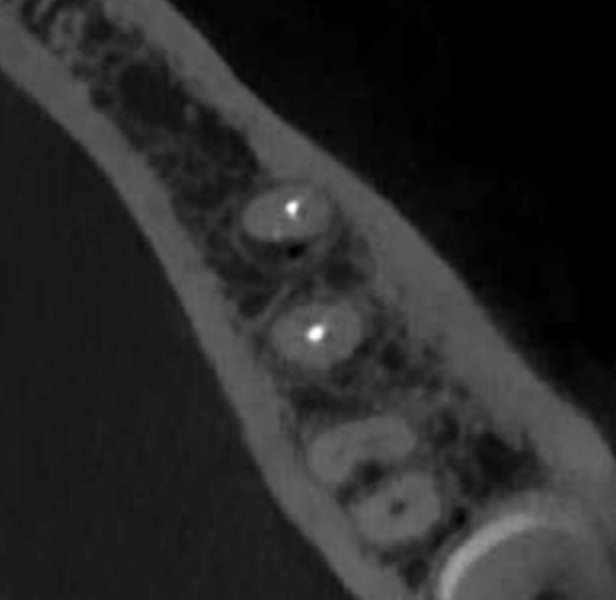

Reco preendo + 4 conductos molar superior